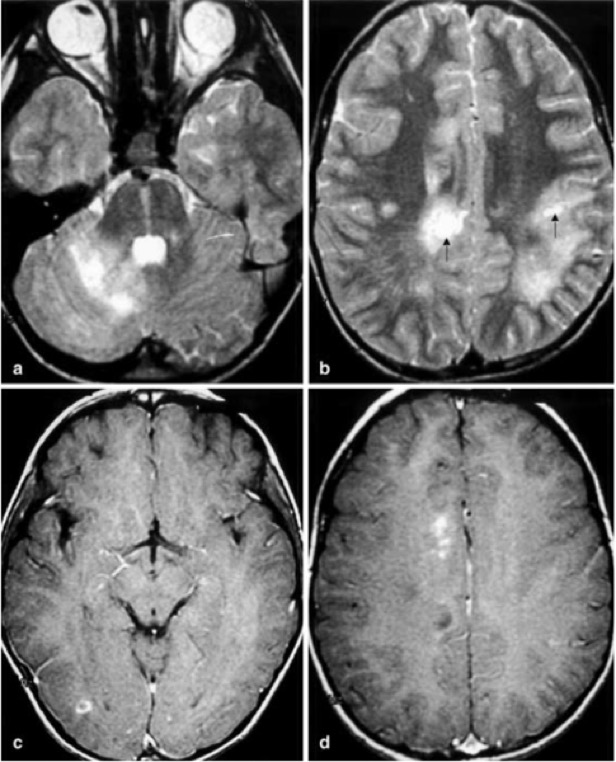

5. IRM cérébrale 0-72h (A répéter après quelques jours si N)

- Pondération T2: DP- T2 SE (PLUS SENSIBLE QUE FLAIR!!!)

- FLAIR (encéphale) STIR (moelle)

A. Lésions démyélinisantes du SNC (Cv: SB et SG, Cvt, TC, Moe, NGC)

- Lésions punctiformes à > 1-2cm voire forme pseudo-tumorale

- hyperT2/Flair => des couronnes radiantes, des noyaux lenticulaires, thalamus, loci niger

=> SB péri-V et sous corticale

- Multiples, bilatérales, ASYMÉTRIQUES et MAL DÉFINIE

- récentes et du MÊME âge

- C- (rarement C+)

Lésions hyper FLAIR multiples

Patches hyper T2 bilat asym + NGC + CC + TC

Pas de DWI

C+ : 30% des cas (ring-like, focal and diffuse/patchy)

- • Substance blanche profonde du cerveau et du cerveau

- • de la substance blanche sous-corticale

- • du thalami

- • du tronc cérébral

- • des ganglions de la base

- • du cortex cérébral

- • de la moelle épinière